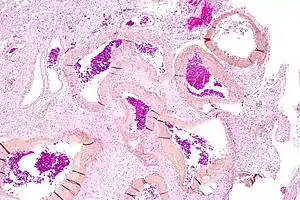

Micrograph of an arteriovenous malformation in the brain. HPS stain. | |